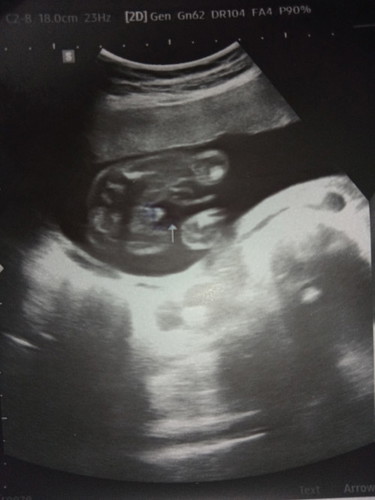

แบบนี้ผู้ชายใช่ไหมคะแม่ๆ

ใช่จู๋ไหมคะแม่ๆ อัลตร้าซาวด์ตอนอายุครรภ์ 20+5Weekค่ะ #ทีมธันวาคม67ค่ะ #ขอบคุณล่วงหน้าสำหรับความคิดเห็นค่ะ

ในภาพ แม่ได้ลูกชายค่ะ ส่วนบ้านนี้ ไปซาวมาเมื่อวานค่ะ ได้ลูกสาวค่ะ 20 วีคพอดี #ท้องลูกคนแรกค่ะ

ผู้ชายค่ะแม่ ยินดีด้วยนะคะ☺️บ้านนี้ตอนซาวด์ก็แบบนี้เลยออกมาเป็นผู้ชายทะเล้นมาก